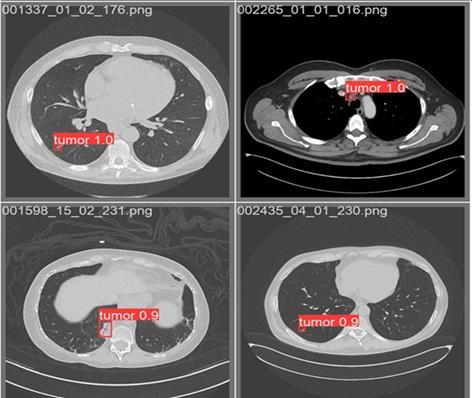

Yolov5isaonestageobjectdetectorsothatitdetectsand classifiestheobjectsliketumoursinonepass,thismeansit predicts bounding boxes and class probabilities simultaneously.soherethereisaminimallossinaccuracy. Previous models like faster R-CNN first identify the object locations(proposals) and then classify these proposals. Thus, Yolov5 minimizes the processing delay and optimizestheperformance.

Thefinaloutputconsistsofboundingboxesandconfidence scoresfordetectedlungnodules.[11][12]

The Xception model which was used for the classification achieved 94.4% accuracy in distinguishing between varioustypes oflungcancer cells.Theyolov5 architecture which was used for detection achieved 99% accuracy for lung nodule localization which also minimizes the false positives. These two models make finding and correctly diagnosinglungcancermorereliableandaccurate.